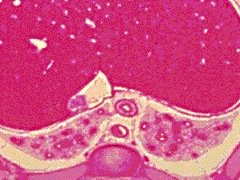

E3:

R dome of diaphragm. Liver. R long middle and

inferior lobes. L long superior and inferior lobes.

Xiphoid process.